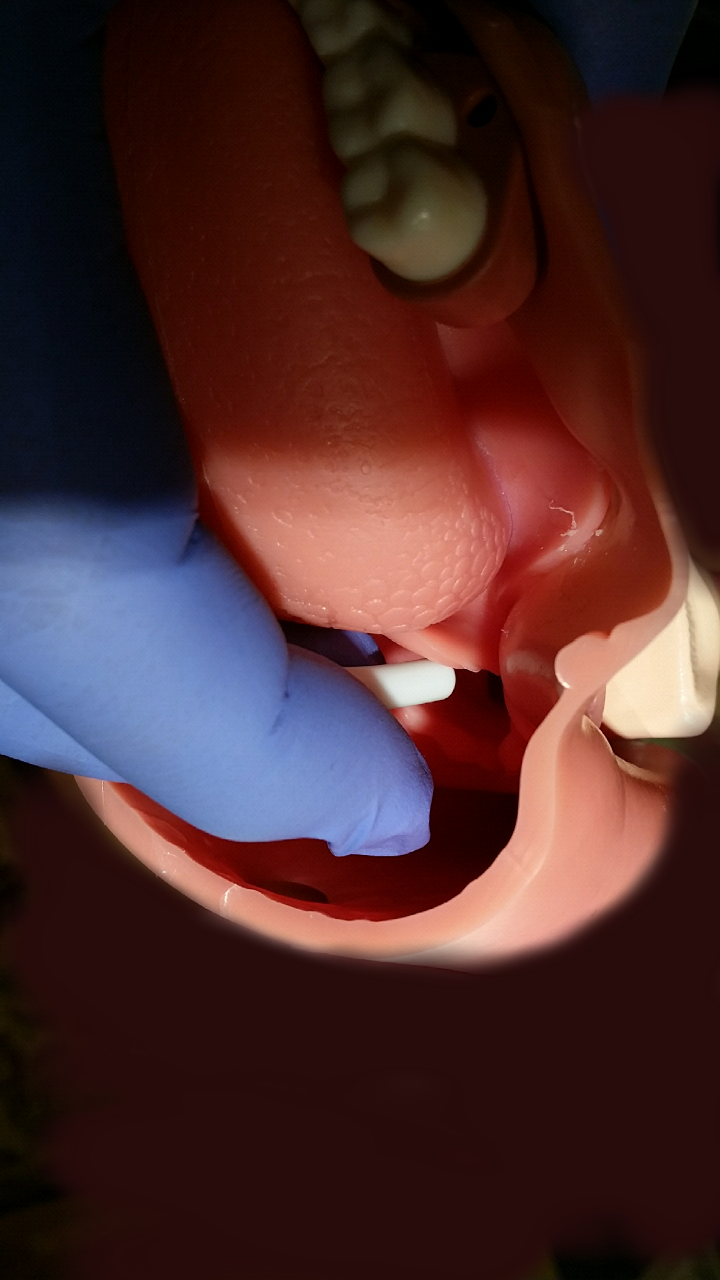

Intubation and extraglottic airway equipment still has not arrived. Pulling out your bougie and tube, you take out the patient’s dentures and use the oral airway as a bite block. You find the epiglottis with your middle and index fingers inserted into the mouth and guide the bougie into the glottic opening feeling tracheal ticks and hold-up to confirm. The tube slides over the bougie. Successful ventilation occurs without chest compressions missing a beat and the code continues.

patient, remove dentures - Insert middle and index fingers of left hand in patient’s mouth

- Use left hand middle finger to follow the curve of

tongue posteriorly to feel the epiglottis edge

- Lift up epiglottis with your middle finger

- Insert the bougie down lateral side of middle finger between middle finger and index finger

- Use the index finger to put guide bougie into the larynx

(a) After the epiglottis is identified by palpating it with the long finger of the left hand, the bougie is threaded through the glottis and advanced into the trachea. Tracheal clicking elicits tactile vibrations, which confirm tracheal placement of the bougie.

“Standing at the side of the patient (face to face), the left index and long fingers were inserted into his mouth and along the tongue to a depth that made it possible to digitally identify the epiglottis, the rima glottis, and posterior cartilages. With the fingers pressing the epiglottis against the pharyngeal wall, a bougie was passed along the axis of the long finger (stabilizing it between the index and long finger) and inserted through the glottis, where it elicited tracheal clicking, and was then advanced to a depth of 25 cm from the corner of the lip. The endotracheal tube was then passed over the bougie into the trachea, which was confirmed by capnography. The digital intubation required less than 1 minute.” [1]